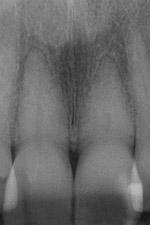

Figure 1 shows a radiograph of a typical maxillary first molar. Upon extraction, the apical anatomy was immediately studied and photographed under a global microscope (Figure 2, Figure 3, Figure 4, Figure 5 and Figure 6). That is a take-home lesson; the extracted teeth should be studied with loupes or microscopes. These photographs demonstrate an important lesson. The two-dimensional radiograph shows three roots. In reality, however, a significant percentage of maxillary first and third molars—80% in some studies—have four roots and four or more canals. 1,2 While the MB and MP (MB-2) roots are usually fused, their morphology is unique. For diagnostic, access, and shaping purposes, it is safer to think of them as separate roots. Wisdom teeth often exaggerate the anatomic features of first and second molars, and a significant percentage of maxillary third molars have four distinct roots. The author's personal bias is to consider most maxillary first the radiographic apex of the tooth. The use of the radiographic root apex for use as the reference point for measuring the apical extent of the root filling is the common standard, yet has been criticized because of the poor correlation between the location of this point and the actual canal foramen. 5 The illustrations used in advertising and manufacturer's "tip cards" only further the notion of simple foramen anatomy. While simple anatomy is often the case with incisor teeth, a quick perusal of the posterior teeth in Brown and Herbransen's Dental Anatomy & 3D Interactive Tooth Atlas demonstrates that a significant portion of the foramen exit short of the apex and have multiple foramina. 6 The same extracted tooth in Figure 2 demonstrates that the palatal foramen is more than a millimeter short of the radiographic apex. If this tooth were filled to the constriction, which for arguments sake is 0.75 mm from the foramen, a straight-on radiograph would depict the fill as being at least 2 mm "short."

Fig. 1 Periapical radiograph of maxillary left first molar. Two-dimensional images lead to two-dimensional thinking.

Figure 1